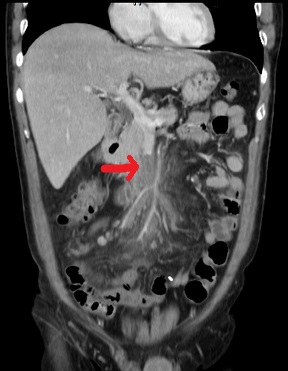

【113-2 醫學(三) 第74題】56歲男性病患,過去有高血壓病史,突然有發燒、嘔吐與腹痛的症狀,緊急安排了電腦斷層檢查影像如附圖,下列何者為最可能的診斷?

病患急性腹痛、發燒、嘔吐,電腦斷層影像顯示上腸繫膜靜脈內有血栓形成,這是診斷上腸繫膜靜脈血栓的關鍵線索。

選項拆解

-A:盲腸炎(acute appendicitis)通常表現為右下腹痛,電腦斷層會顯示闌尾腫脹發炎。本影像未見闌尾病變。